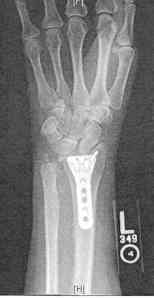

I’ve recently resumed working in my studio after months recuperating from my fall and broken wrist in January. It was a bad break that required surgery to put in a plate and several screws. Two orthopedic surgeons told me the break was too complicated for them to fix and that I needed a hand specialist. Now, I look at the x-ray of my wrist and appreciate the intricacies of the hand surgeon’s fine detailed work. I’m glad that I waited the ten days after the break to have her do the surgery in Boston. Today, after 2 months of hand therapy, I’ve regained most of my wrist’s rotation, but still have limited flexibility and strength. Even though the break was in my subdominant left hand, I need the full use of my wrist to hold materials that I stitch with my right. As I work, I can feel the tendons in my hand and wrist pulling and aching, but I’m determined to sew! My physical therapist told me that she will work with me another month, to see if we can get back as much use as possible.

close to ten years ago, i shattered my left wrist in a biking accident. it was called a comminuted fracture. like you, i was lucky to have an orthopedic surgeon who knew what he was doing and he did it well! my x-ray looks so much like yours. i felt as if i had a bionic wrist with the plate and screws. i regained full use and range of motion of my wrist and it is even stronger now than my dominant right. i am so happy for you that you are recovering and i want you to know that your wrist will feel better and pain free soon. a year out from my surgery i was astounded to be pain free. the most frustrating part of injury and recovery were the little things i took for granted before the bike accident… shampooing my hair, getting dressed, being able to do the dishes! (?) ! i have so much empathy for what you’re going through.

Sheila, thanks for sharing the story of your broken wrist and the successful outcome. I wasn’t sure about putting the x-ray on the post, thinking it might be too graphic, but there’s nothing like a photo to communicate what’s real. I wish that I could sign all of the books in your collection!